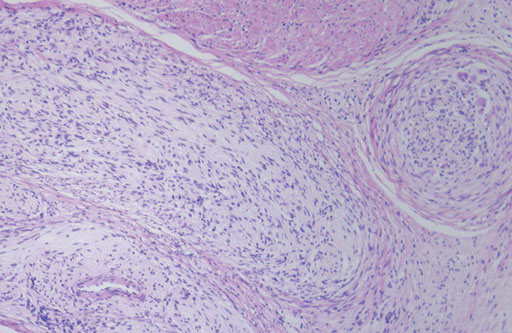

病理では膀胱の筋層内に瀰漫性に増生する神経線維腫が認められる.

• 図4 HE染色(×40)

• 図5 HE染色(×100)